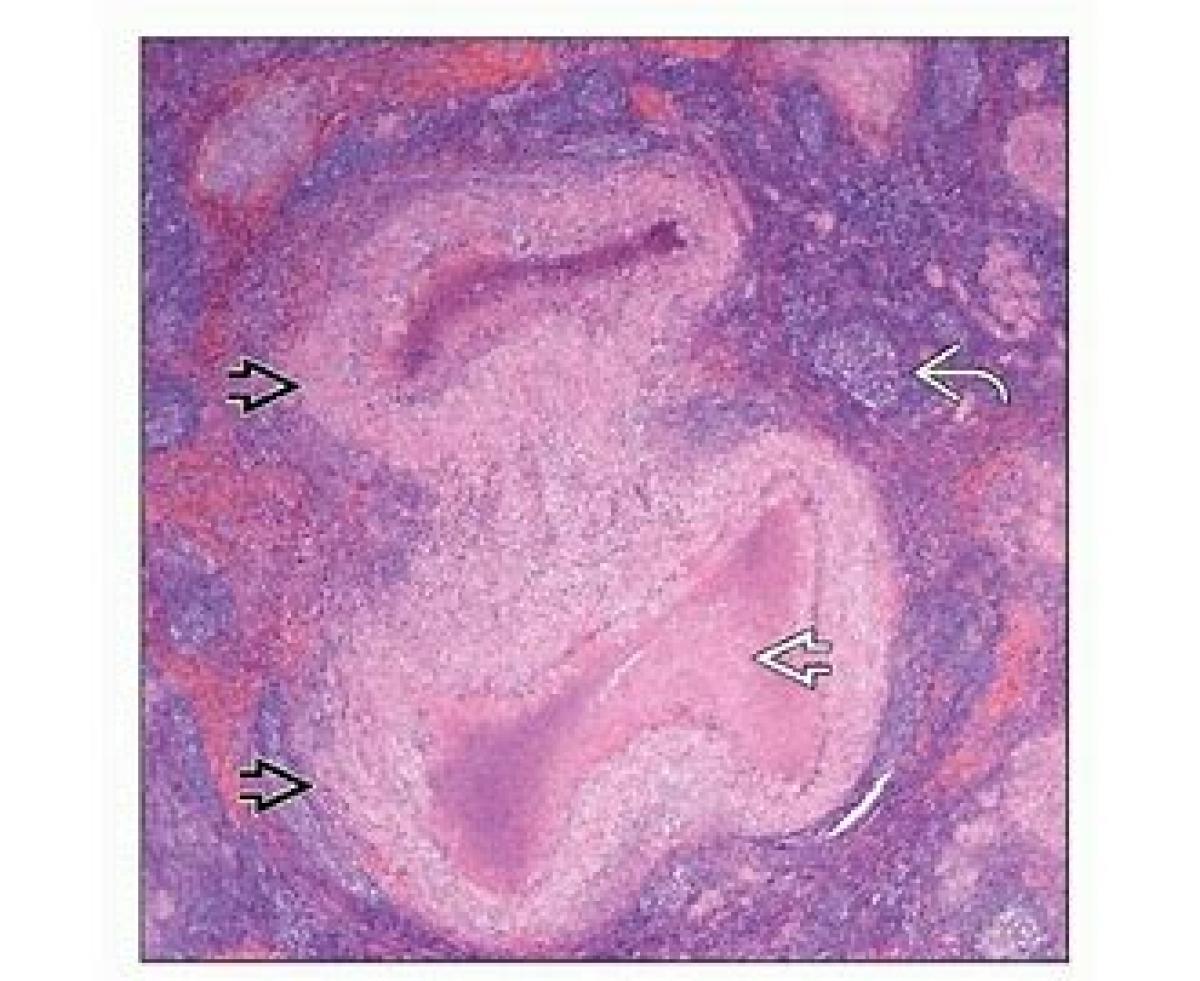

Cat Scratch Disease

بیماری خراش گربه از بیماریهای منتقله از حیوانات به انسان است. انتقال بیماری در بیش از ۹۰ درصد موارد در اثر پنجه زدن و گاهی لیس زدن بچه گربه به بدن کودک است و گهگاه نیز توسط سگها و یا خار و تراشههای چوب که با سگ و گربه در ارتباط بوده منتقل میشود. این باکتری گربه را دچار بیماری نمیکند و در بزاق گربه زندگی میکند تا از راه خراش یا گازگرفتن گربه بهخصوص بچه گربه به انسان منتقل میشود. عامل این بیماری معمولاً خوش خیم باکتری داخل سلولی Bartonella henselae است. نزدیک به نیمی از گربهها در طول زندگی خود مدتی ناقل این باکتری بودهاند.